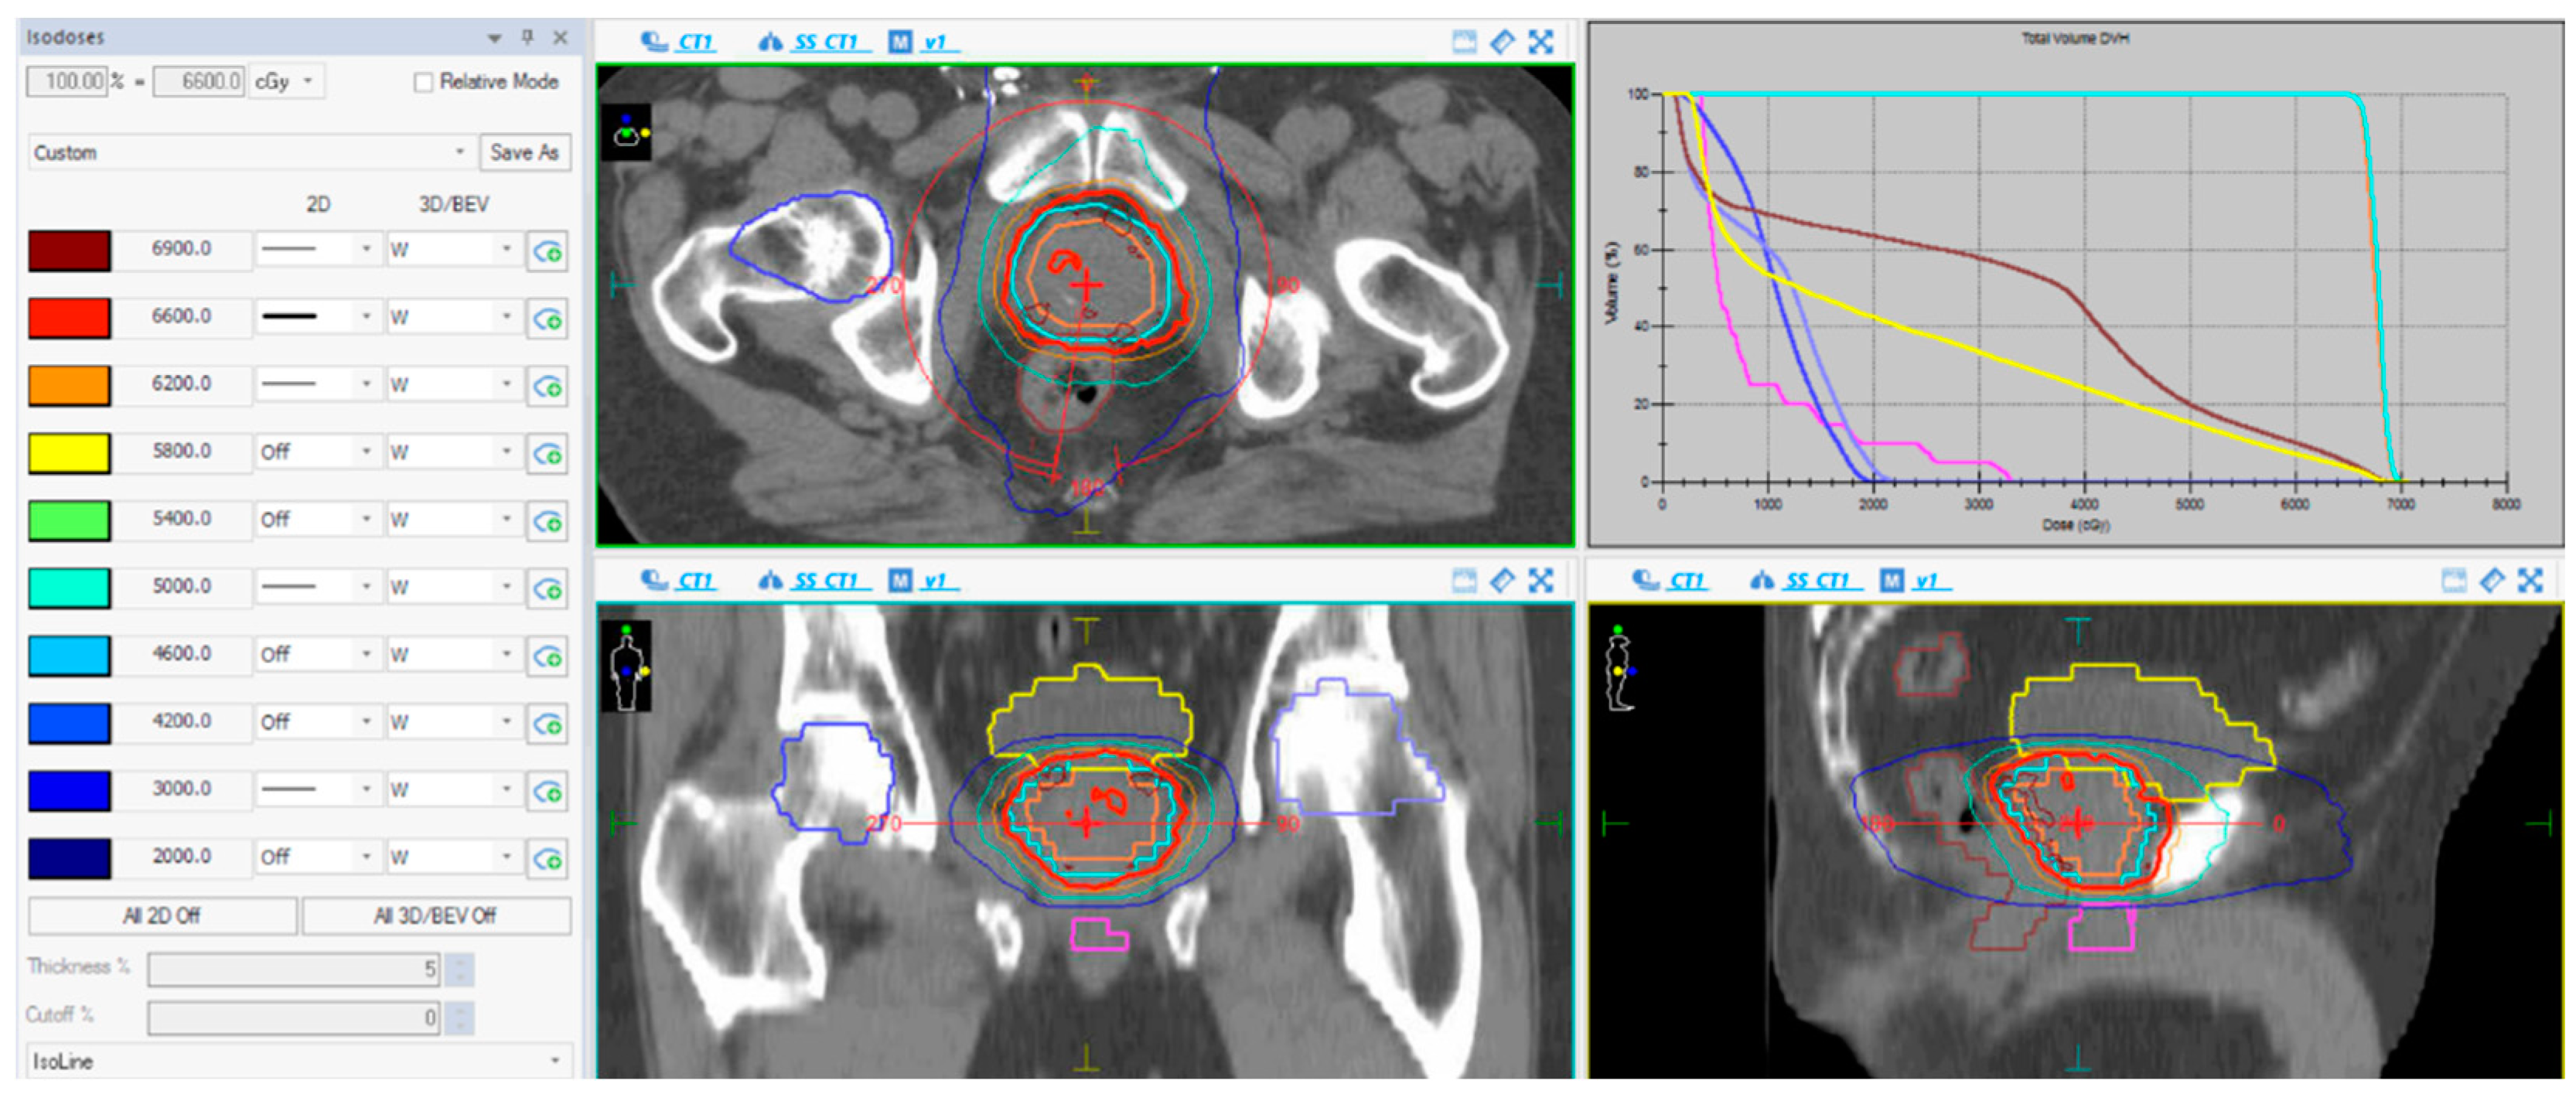

2.2. Radiotherapy